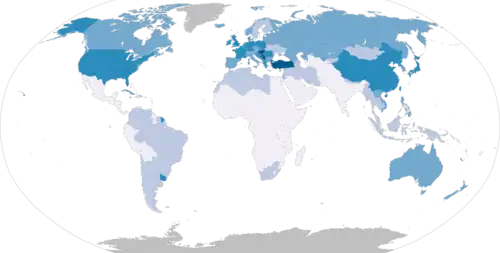

Around 19% of people diagnosed with lung cancer survive five years from diagnosis, though prognosis varies based on the stage of the disease at diagnosis and the type of lung cancer.[5] Prognosis is better for people with lung cancer diagnosed at an earlier stage; those diagnosed at the earliest TNM stage, IA1 (small tumor, no spread), have a two-year survival of 97% and five-year survival of 92%.[58] Those diagnosed at the most-advanced stage, IVB, have a two-year survival of 10% and a five-year survival of 0%.[58] Five-year survival is higher in women (22%) than men (16%).[5] Women tend to be diagnosed with less-advanced disease, and have better outcomes than men diagnosed at the same stage.[59] Average five-year survival also varies across the world, with particularly high five-year survival in Japan (33%), and five-year survival above 20% in 12 other countries: Mauritius, Canada, the US, China, South Korea, Taiwan, Israel, Latvia, Iceland, Sweden, Austria, and Switzerland.[60]

Lung cancer incidence varies by geography and sex, with the highest rates in Micronesia, Polynesia, Europe, Asia, and North America; and lowest rates in Africa and Central America.[98] Globally, around 8% of men and 6% of women develop lung cancer in their lifetimes.[2] The ratio of lung cancer cases in men to women varies considerably by geography, from as high as nearly 12:1 in Belarus, to 1:1 in Brazil, likely due to differences in smoking patterns.[99]